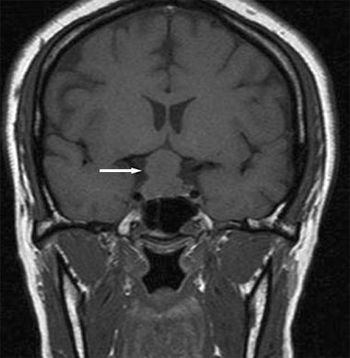

A 26-year-old woman at 30 weeks’ gestation presented to the emergency department with a throbbing frontal headache of 1 month’s duration. She had also had peripheral blurred vision for the past 2 weeks. Acetaminophen initially decreased her pain but was no longer effective. She had had a previous miscarriage.